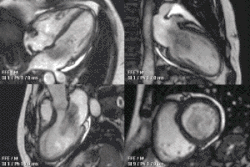

A CMR study typically comprises a set of sequences in a protocol tailored to the specific indication for the exam.[21] A study begins with localisers to assist with image planning, and then a set of retrospectively-gated cine sequences to assess biventricular function in standard orientations. Contrast medium is given intravenously to assess myocardial perfusion and LGE. Phase contrast imaging may be used to quantify valvular regurgitant fraction and shunt volume. Additional sequences may include T1 and T2-weighted imaging and MR angiography. Examples are below:

Heart function using cine imaging

Functional and structural information is acquired using bSSFP cine sequences. These are usually retrospectively-gated and have intrinsically high contrast in cardiac imaging due to the relatively high T2:T1 ratio of blood compared to myocardium. Images are typically planned sequentially to achieve the standard cardiac planes used for assessment. Turbulent flow causes dephasing and signal loss allowing valvular disease to be qualitatively appreciated. The left ventricular short axis cines are acquired from base to apex and are used for quantifying end-diastolic and end-systolic volumes, as well as myocardial mass. Tagging sequences excite a grid pattern that deforms with cardiac contraction allowing strain to be assessed.